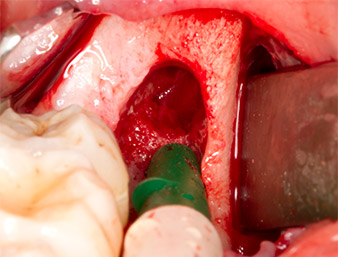

After block and local anaesthesia, the operating site was opened up and the soft tissue exposed for buccal retromolar access (Fig. 3).

The tissue above the root remnant was not completely ossified and consisted for the most part of granulation tissue modified by inflammation (Fig. 4).